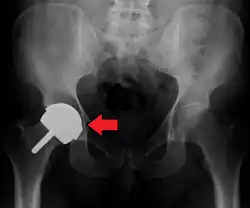

Configuration

Post-operative projectional radiography is routinely performed to ensure proper configuration of hip prostheses.

The direction of the acetabular cup influences the range of motion of the leg, and also affects the risk of dislocation.[16] For this purpose, the acetabular inclination and the acetabular anteversion are measurements of cup angulation in the coronal plane and the sagittal plane, respectively.